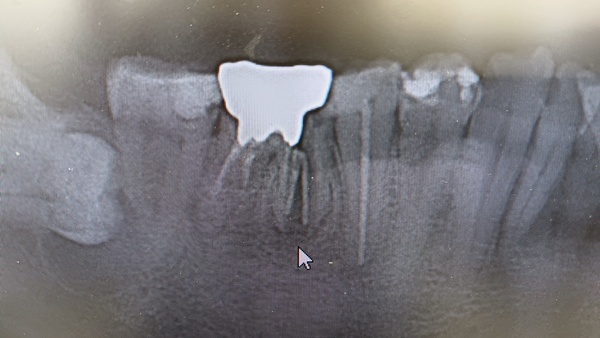

歯の根の部分が割れてしまう歯根破折は、むし歯、歯周病に次いで歯を失う原因になっています。治療が難しく、歯根破折となると抜歯してしまう歯科医院が多いものです。歯根破折の歯全てが救われるわけではありませんが、稀に助かる歯も数多く存在しますので、是非イナグマ歯科にご相談ください。

歯根破折とは

歯の根が割れてしまうトラブルのことです。歯を失う原因はこれまでほとんどがむし歯と歯周病といわれていましたが、最近では歯根破折が原因で歯を抜かなければならないケースが増えています。

歯根破折になると、お口の中の細菌が割れ目を通って歯や歯ぐき、さらには骨の中まで入り込み、歯の痛みや歯ぐきの腫れを引き起こします。初期段階ではレントゲンで判断することが難しいために、知覚過敏と診断されてしまうことが多く見られます。